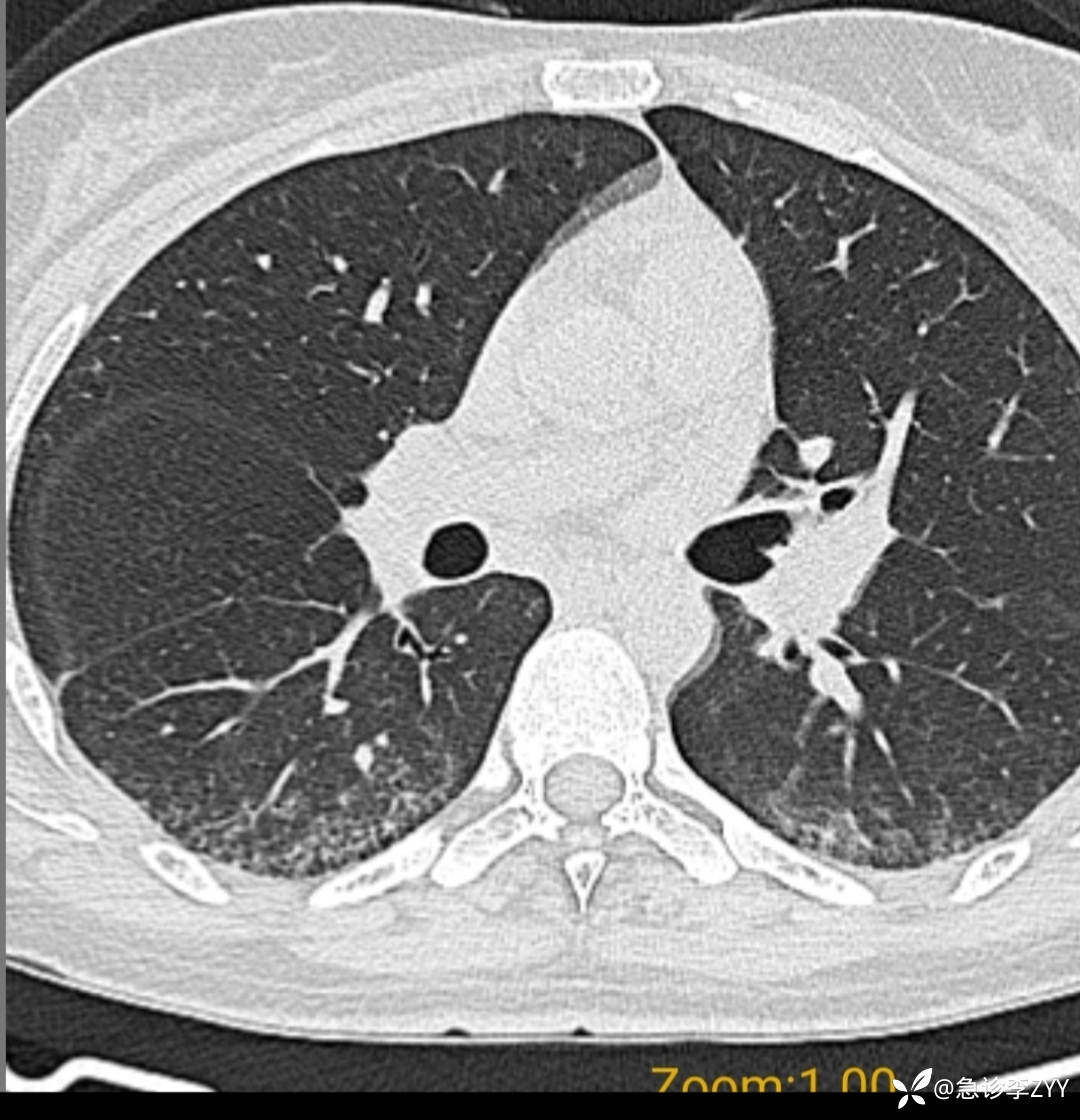

患者,女,28岁,干咳,胸闷伴活动气喘9月余,到急诊科就诊。请教老师,目前胸部CT等检查后可考虑类风湿致普通型间质肺炎?